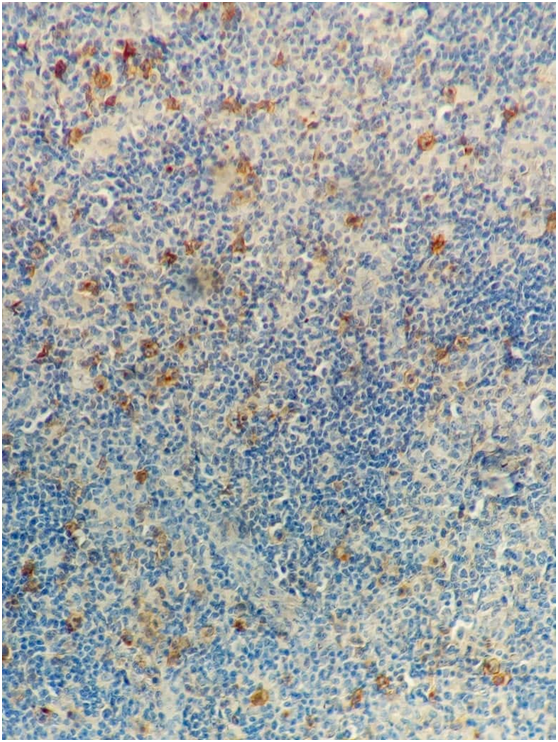

A biopsy is performed for the retro-auricular lymphadenopathy, and finally histopathological and immunohistochemical examination confirmed the diagnostic of nodular sclerosing Hodgkin's disease stage IV (Ann Arbor staging) (Figure 2). The tumor’s cells were expressing CD15, CD30 (Figure 3 & 4). The patient is then transferred to the hematology department for therapeutic management.

Figure 3 HES staining - Low magnification: Expression of CD15 by scattered pleomorphic tumor cells (with CD15 expression in approximately 20 % of tumor cells)